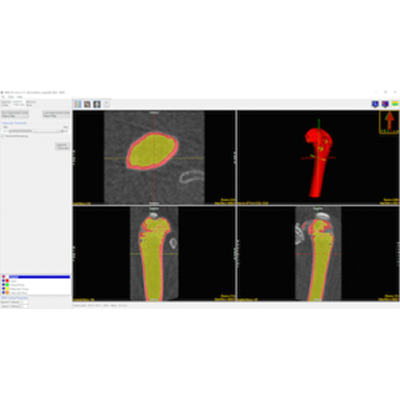

Cortical Bone Segmentation

Once the image data is loaded the BMA add-on will conduct a preliminary segmentation which will allow the module to identify the cortical shell, cortical pores and trabecular tissue regions.

Trabecular Bone Segmentation

Upon user approval the add-on will now complete the segmentation process by identifying the trabecular bone in the trabecular region. Two new regions, the trabecular bone and intra-trabecular space will be derived.

Calculate Bone Measurements

Measurements are automatically calculated for the trabecular and cortical bone and output in several comma-separated value (.csv) files. A utility is also provided to convert CT numbers (HUs) to Bone Mineral Density (BMD) in units of mg/CC.